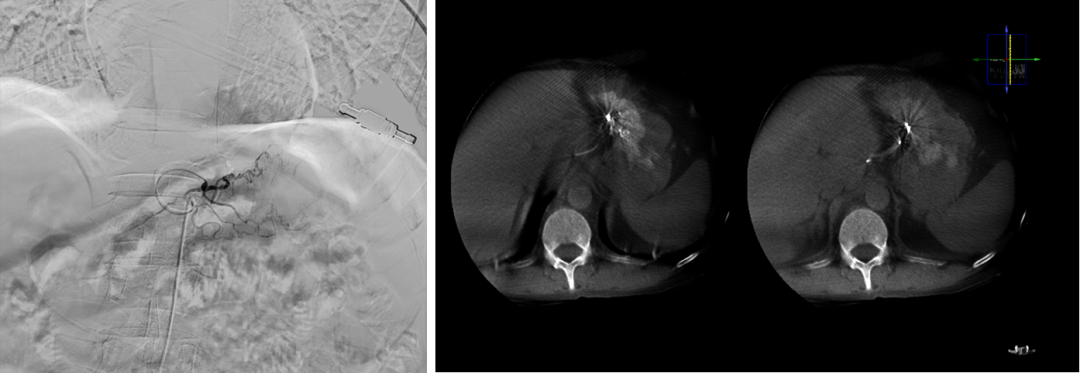

肿瘤性出血:介入控制与局部治疗并举

胃癌、结直肠癌等肿瘤常伴发出血。介入栓塞不仅能快速止血,使用载药微球等材料还能实现局部化疗,提升肿瘤控制率,改善患者贫血状态,为后续治疗创造条件。

图:直肠肿瘤

图:胃癌出血